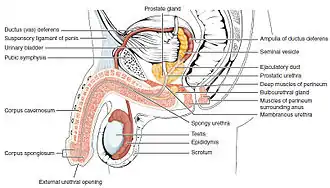

The urethra transports urine from the bladder to the outside of the body. This image shows (a) a female urethra and (b) a male urethra. | |

Male

In the human male, the urethra is on average 18 to 20 centimeters (7.1 to 7.9 inches) long and opens at the end of the external urethral meatus.[8]

The urethra is divided into four parts in men, named after the location:[8]

| pre-prostatic urethra | This is the intramural part of the urethra surrounded by the internal urethral sphincter and varies between 0.5 and 1.5 cm in length depending on the fullness of the bladder. | Transitional |

| prostatic urethra | Crosses through the prostate gland. There are several openings at the posterior wall : (1) the ejaculatory duct (2 lateral) receives sperm from the vas deferens and ejaculate fluid from the seminal vesicle, (2) prostatic sinus which has openings for several prostatic ducts where fluid from the prostate enters and contributes to the ejaculate, (3) the prostatic utricle, which is merely an indentation. These openings are collectively called the verumontanum (colliculus seminalis)

The prostatic urethra is a common site of obstruction to outflow of urine in BPH patients |

Transitional |

| membranous urethra | A small (1 or 2 cm) portion passing through the external urethral sphincter. This is the narrowest part of the urethra. It is located in the deep perineal pouch. The bulbourethral glands (Cowper's gland) are found posterior to this region but open in the spongy urethra. | Pseudostratified columnar |

| spongy urethra (or penile urethra) | Runs along the length of the penis on its ventral (underneath) surface. It is about 15 to 25 cm in length,[9] and travels through the corpus spongiosum. The ducts from the urethral gland (gland of Littré) enter here. The openings of the bulbourethral glands are also found here.[10] Some textbooks will subdivide the spongy urethra into two parts, the bulbous and pendulous urethra. The urethral lumen runs effectively parallel to the penis, except at the narrowest point, the external urethral meatus, where it is vertical. This produces a spiral stream of urine and has the effect of cleaning the external urethral meatus. The lack of an equivalent mechanism in the female urethra partly explains why urinary tract infections occur so much more frequently in females. | Pseudostratified columnar – proximally, Stratified squamous – distally |

There is inadequate data for the typical length of the male urethra; however, a study of 109 men showed an average length of 22.3 cm (SD = 2.4 cm), ranging from 15 cm to 29 cm.[11]

Ejaculation

The male urethra is the conduit for semen during sexual intercourse.[2] Urine is removed before ejaculation by pre-ejaculate fluid – called Cowper's fluid – from the bulbourethral gland.[16][17]

Position of the urethra in males

Position of the urethra in males Transverse section of the penis